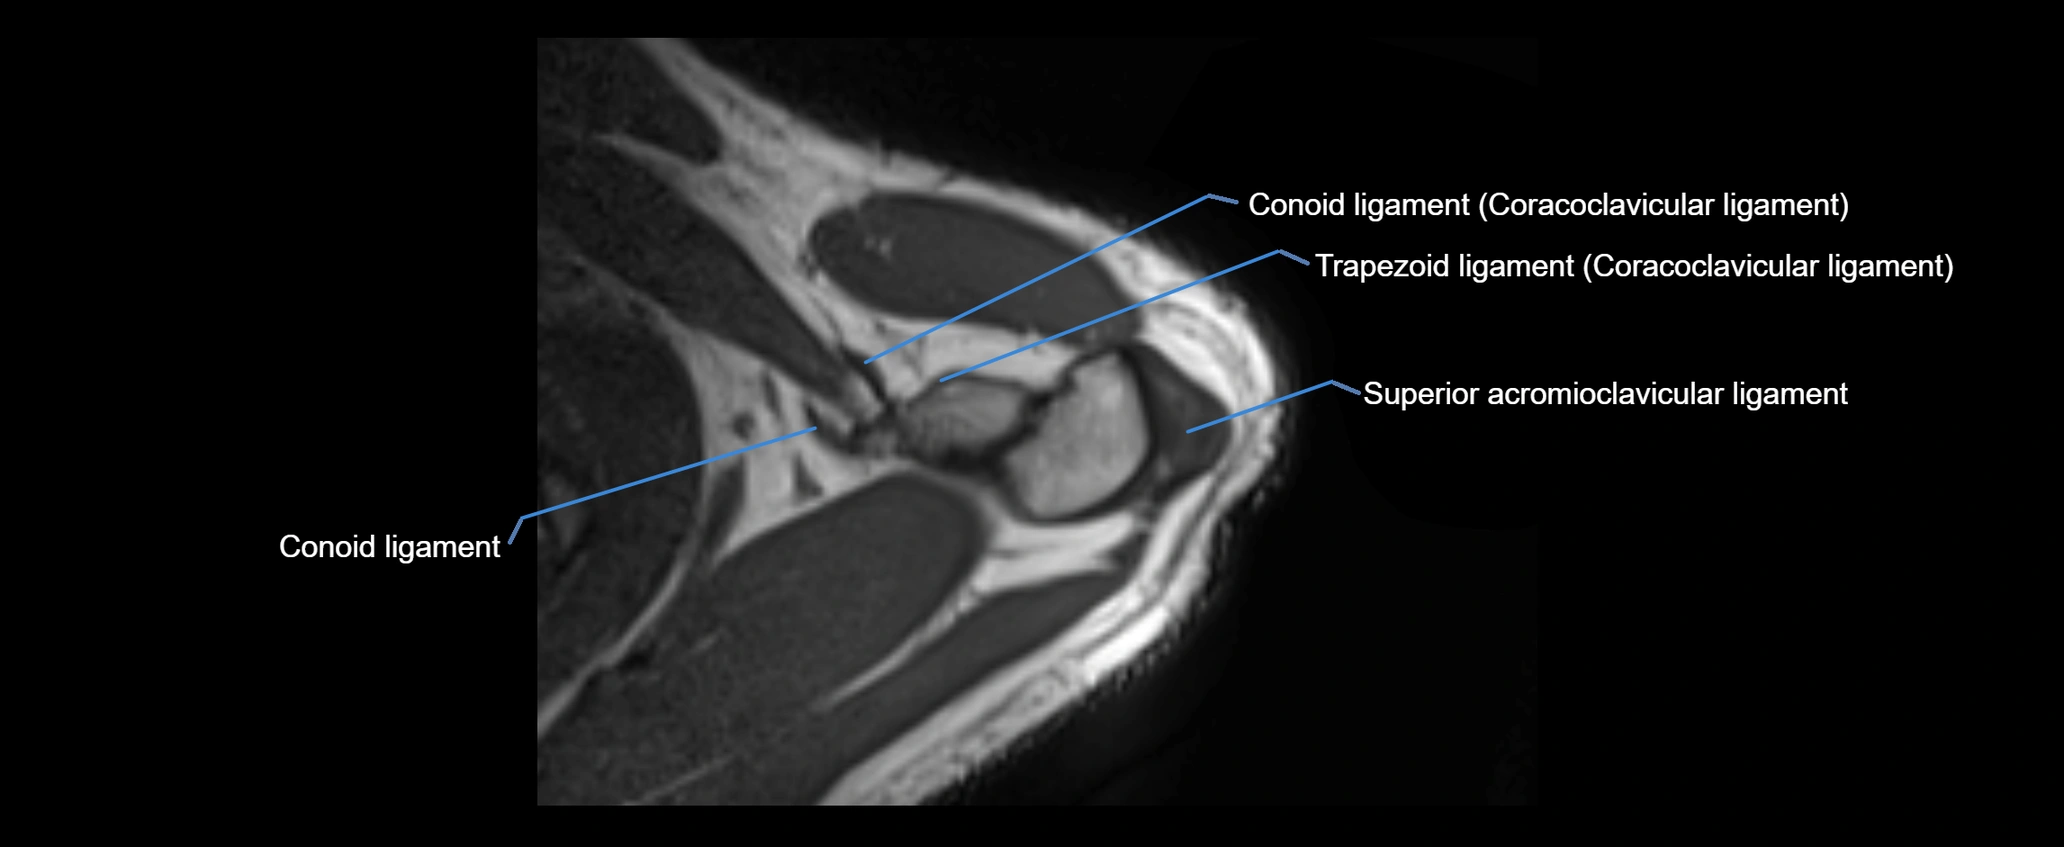

MRI images

image